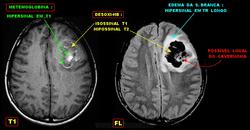

Кавернома.

Внутрижелудочковая кавернома.